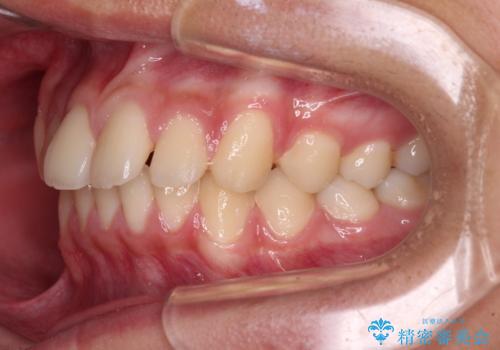

- 前歯のデコボコと隙間を気にして来院された高校生の患者様です。

下顎前歯が上顎前歯を突き上げるような咬み合わせとなっており、その影響で上顎正中に隙間ができている状態でした。

叢生の程度は軽度であり、本人もしっかりと使用する自信があるとのことだったので、インビザラインによる矯正治療を行うこととしました。

突き上げによる隙間を予防する為に、深い咬み合わせを改善するような治療計画としました。咬み合わせを改善させることはできましたが、隙間は後戻りしやすいので、通常の下顎前歯のみではなく、上顎前歯2本もワイヤーで保定を行いました。